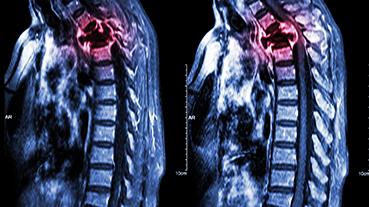

Innovative technologies and alternatives to traditional treatments are transforming the diagnosis and management of neurological conditions. In 2025, NewYork-Presbyterian physicians and surgeons from Columbia and Weill Cornell Medicine used sonication and convection-enhanced delivery to penetrate the blood-brain barrier, validated an adjunctive treatment for subdural hematoma, broadened access to spine surgery, advanced experimental therapies for neurodegenerative diseases, and more. Our specialists have been steadfast in reshaping the fields of neurology and neurosurgery in the pursuit of better patient outcomes and enhanced quality of care.

From cutting-edge research to compassionate patient practice, neurologists and neurosurgeons from Columbia and Weill Cornell Medicine are at the forefront of developing and applying the most advanced approaches to treat debilitating conditions affecting the brain and spine. With a broad range of focus on neurodegenerative and neurovascular disorders to malignant tumors, our innovative and advanced care is leading to new treatment options and enabling patients to achieve the best possible outcomes.